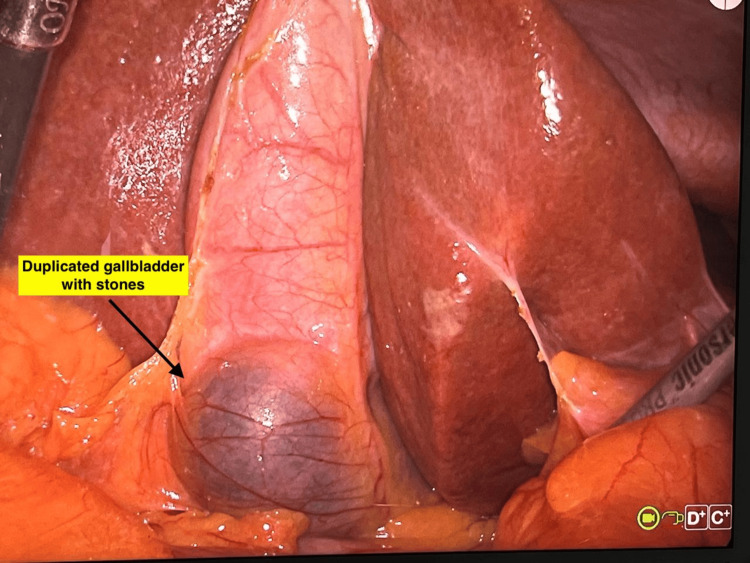

ERCP revealed a CBD of 8 mm with dilated intrahepatic biliary radicals. However, there was no stone in the CBD. Biliary sphincterotomy was performed, followed by placement of a double pigtail plastic biliary stent. Intravenous antibiotics were administered for seven days. Subsequently, the patient underwent laparoscopic cholecystectomy. Intraoperatively, mild adhesions were encountered. However, the cystic duct was clearly identified and dissected, allowing for successful cholecystectomy (Figure 5).

Inspection of the resected specimen revealed duplication of the gallbladder with multiple pigment stones in one of the gallbladder sacs (Figures 6, 7).

The gallbladder was bi-lobed with a single cystic duct and cystic artery. The mucosa appeared normal. Microscopic evaluation showed chronic cholecystitis. No malignancy was seen.